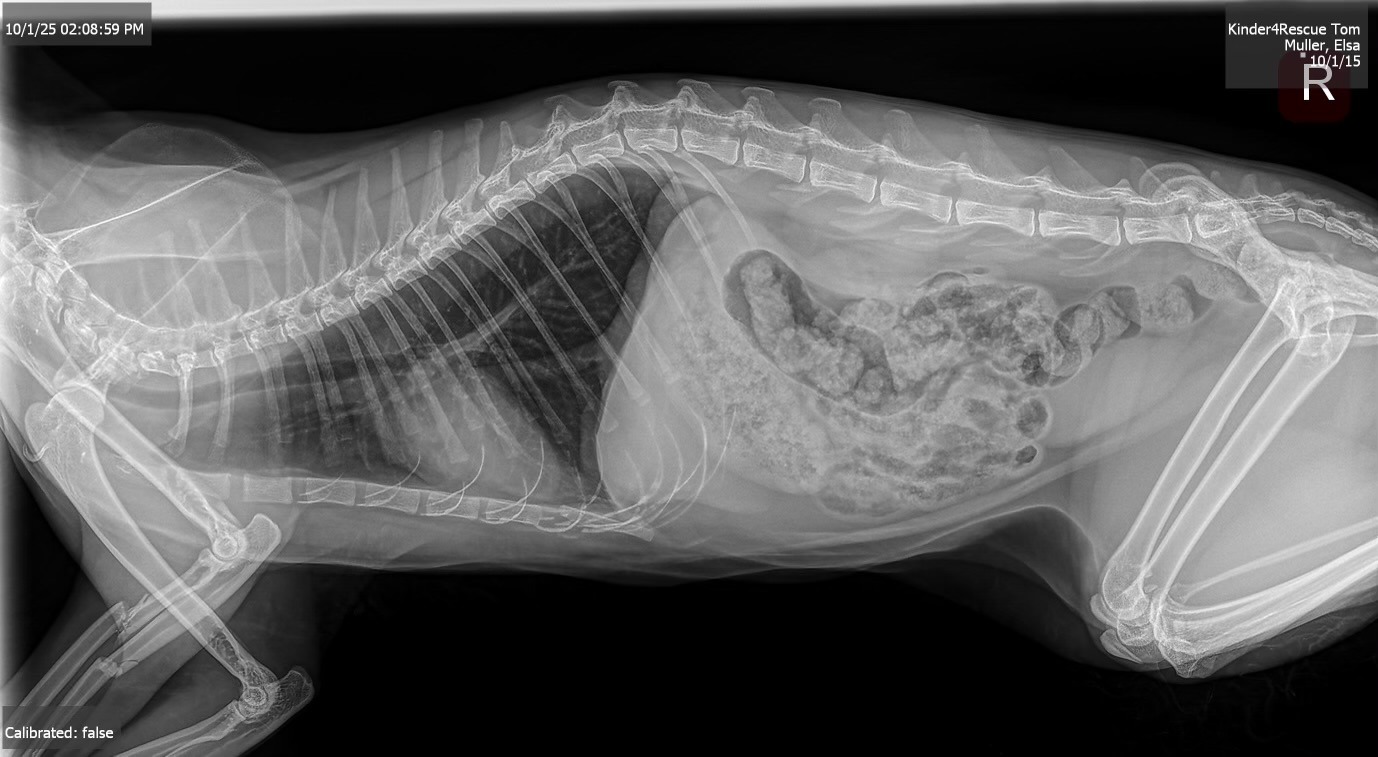

“Family and friends, my beloved Tom had an accident where a large bed frame fell on him and broke his arm. He is in a lot of pain and unfortunately needs surgery. It's going to cost an arm and a leg (no pun intended). Any amount is greatly appreciated.”